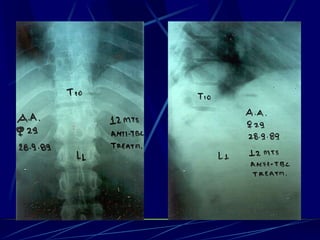

T.B.C.

Φυματίωση της σπονδυλικής στήλης